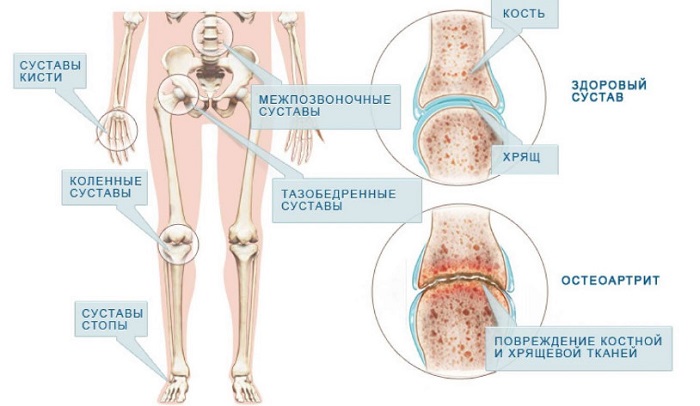

Коленные суставы и ревматоидный артрит: фото и информация